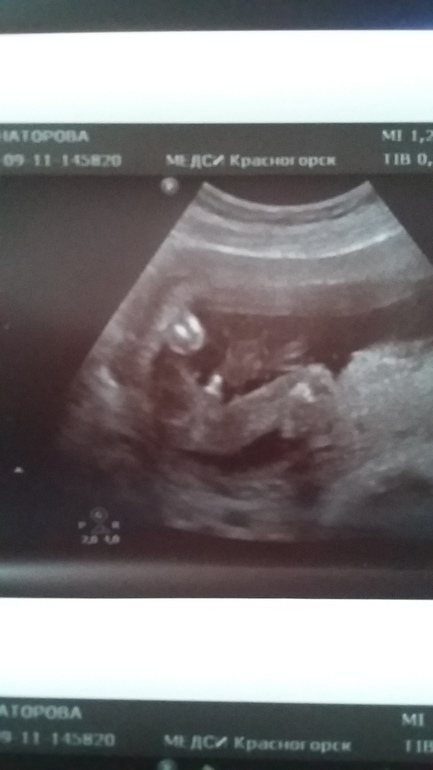

Ура, мы теперь знаем кто в домике живет)))

УЗИ, КТГ, доплерСегодня были на очередном внеплановом узи так как малышок плохо шевелится. А оказалось что мы просто очень тихие и спокойные))) у нас все хорошо, срок 17.5. Весим 203гр. И главная интрига.... тадаааам мы МАЛЬЧИКИ 100%...